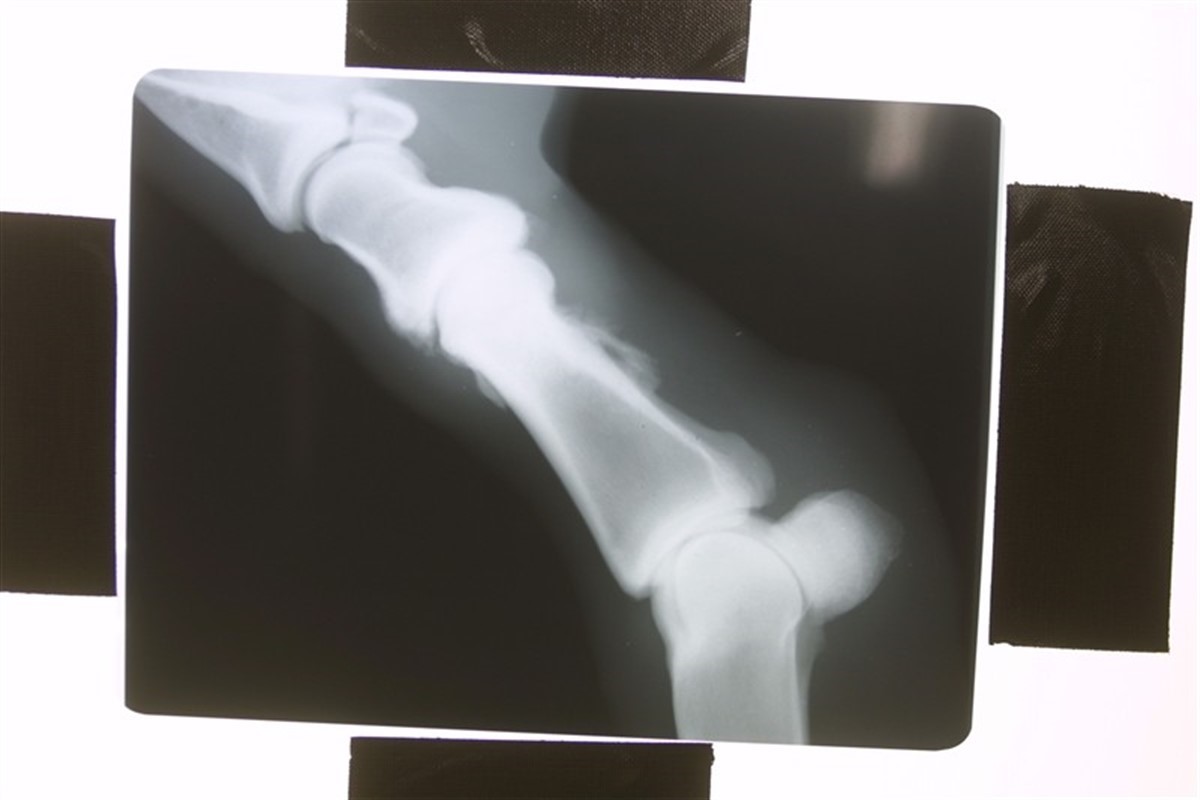

Hør avlskonsulent i Dansk Varmblod Karina Christiansen fortælle om OCD. Klippet stammer fra den faglige beretning 2009.

Ved repræsentantskabsmødet 2009 holdt avlskonsulent Karina Christiansen en fagligt beretning om bl.a. OCD. Hør denne del af beretningen på dette webklip. Klik på det nederste billede i højre side og se klippet.